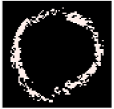

Figure 2 illustrates the result of thresholding, edge detection, region growing [65], level set [66], and active contour (sank), and Figure 3 illustrates the results of clustering using the K-means algorithm.

Figure 2.

(a) VH-IVUS image, (b) thresholding, (c) edge detection, (d) region growing, (e) level set, and (f) active contour (sank).

As illustrated in Figure 2 and Figure 3, unsatisfactory segmentation results are obtained in terms of the overlap borders in the VH-IVUS image, so an accurate algorithm should be developed.